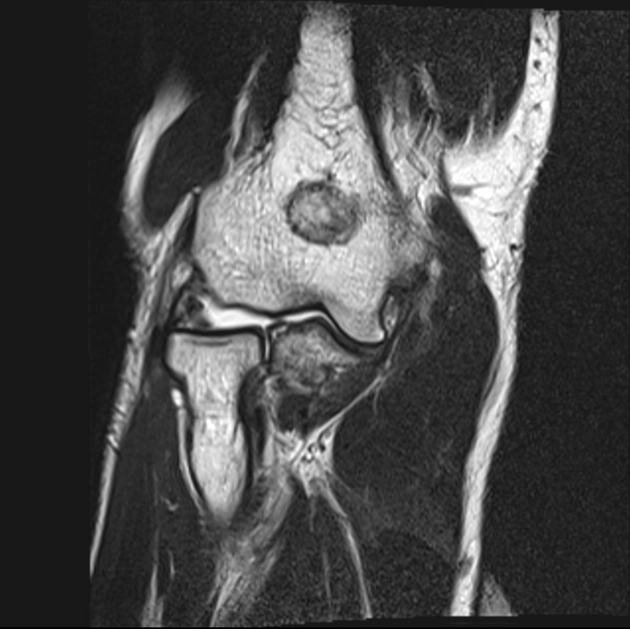

Hội chứng chẹn sau của khuỷu (Posterior Impingement, Elbow)/Hội chứng quá duỗi mỏm khuỷu (Valgus Extension Overload- VEO)